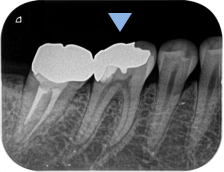

レントゲン・CT画像にて、右下第一大臼歯の根尖部に、明瞭な骨吸収像が認められます。来院時には根管治療の途中の状態でしたが、内部に虫歯が残っており、感染源が取り除けていない状態でした。急性炎症に対して確実な即効性がある治療はありませんが、最大限感染を除去し、細菌の侵入を防ぐことを第一に応急対応を行いました。